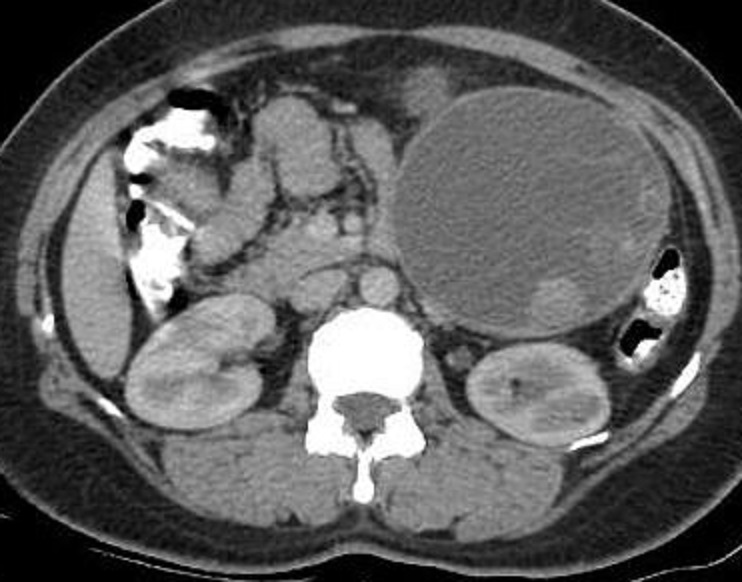

Image

radiologique TDM d'une kyste hydatique active

isthmique du pancreas type I pure avec

aspect lesionnel de masse hypodense de contenue

liquidienne homogene a paroi lisse , regulier situe

au corp du pancreas |

Aspect lesionnel de

formation kystique ovalaire homogene hypodense avec

paroie nette , lisse , regulier d'une kyste

hydatique active de type I de Gharbi . Image

radiologique TDM avec contrast intraveineuse coupe

axiale . Signe de rehaussement de sa paroi peut en

s'observe |